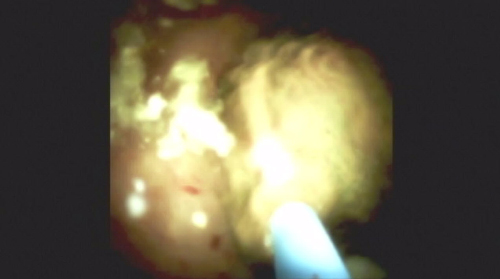

"You can see how well we can visualize the biopsy forceps, and we can do excellent targeted biopsies. And here you see the final diagnosis, which is cholangiocarcinoma."

Robert Hawes, MD

Florida Hospital Center for Interventional Endoscopy

Orlando, Florida